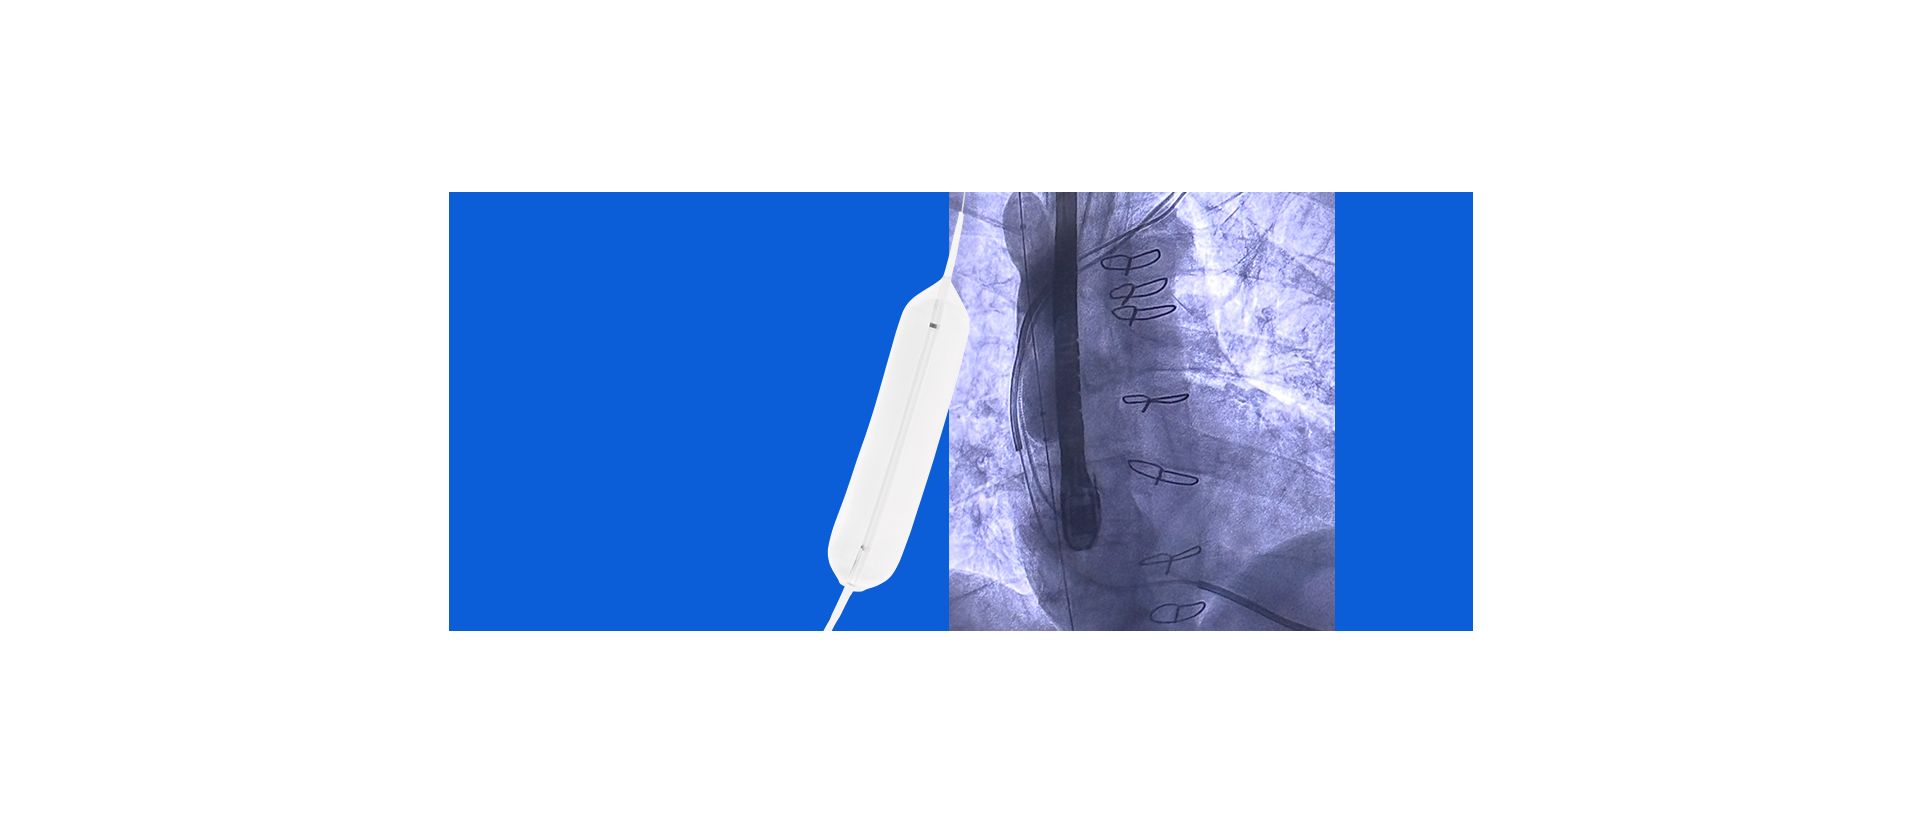

One Platform. Multiple Possibilities. The Future of ICE in EP.

Join the engaging discussion on the evolving role of advanced ICE imaging in electrophysiology. Discover the impact of ICE on workflows and patient care, including concomitant LAAO and ablation procedures, and go beyond conventional 2D ICE with new solutions, all on one platform.